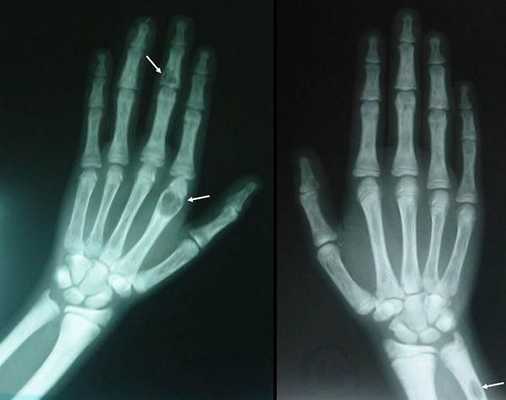

Длительное течение заболевания сказывается на формировании костей. Так, н а поздних стадиях вовремя не диагностированного гиперпаратиреоза наблюдаются:

- разрушение дистальных или концевых фаланг конечностей;

- сужение дистального отдела ключиц;

- очаги разрушения костей черепа;

- бурые опухоли длинных костей.

На поздней стадии костного гиперпаратиреоза происходит размягчение, искривления, патологические переломы (при обычных движениях, в постели) костей, возникают рассеянные боли в костях рук и ног, позвоночнике. В результате остеопороза челюстей расшатываются и выпадают здоровые зубы. Из-за деформации скелета больной может стать ниже ростом. Патологические переломы малоболезненны, но заживают очень медленно, часто с деформациями конечностей и образованием ложных суставов. На руках и ногах обнаруживаются периартикулярные кальцинаты. На шее в области паращитовидных желез можно пальпировать большую аденому.

Рентгенография позволяет обнаружить остеопороз, кистозные изменения костей, патологические переломы. Для оценки плотности костной ткани проводится денситометрия. При помощи рентгенологического исследования с контрастным веществом диагностируют возникающие при гиперпаратиреозе пептические язвы в желудочно-кишечном тракте. КТ почек и мочевыводящих путей выявляет камни. Рентгенотомография загрудинного пространства с пищеводным контрастированием бариевой взвесью позволяет выявить паратиреоаденому и ее местоположнение. Магнитно–резонансная томография по информативности превосходит КТ и УЗИ, визуализирует любую локализацию околощитовидных желез.